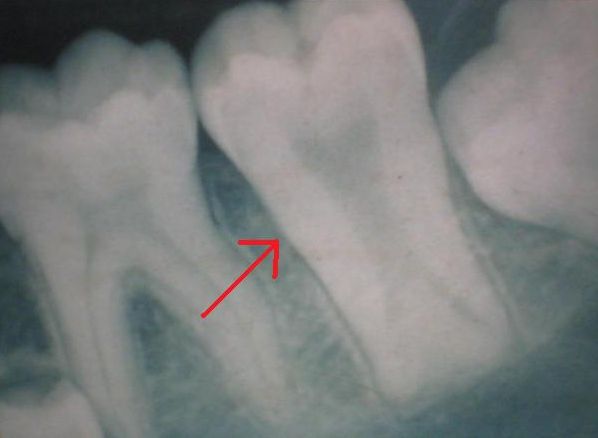

Przy taurodontyzmie (taurodontyzm) wygląd zewnętrzny zęba jest prawidłowy, ponieważ jego trzon i korzenie są przesunięte w głąb wyrostka zębodołowego (brzeg zębodołowy), co sprawia, że zmiana jest niewidoczna klinicznie. Anomalię tę można wykryć wyłącznie na zdjęciu rentgenowskim, gdzie widoczna jest powiększona komora miazgi i skrócone korzenie.

Taurodontyzm (taurodontyzm, „byczy ząb”) to anomalia budowy wewnętrznej zęba, którą można rozpoznać wyłącznie na podstawie zdjęcia rentgenowskiego (radiogramu), ponieważ z zewnątrz ząb zachowuje prawidłowy kształt i rozmiar.

Charakterystyczną cechą taurodontyzmu jest poszerzona komora miazgi (pulpa dentis) o kształcie prostokątnym, wydłużony trzon zęba (corpus dentis) oraz skrócone korzenie i kanały korzeniowe (radices et canales radiculares). W efekcie korona zęba (corona dentis) pozostaje prawidłowej wielkości, ale cała struktura zęba wygląda na „wydłużoną” w kierunku wierzchołków korzeni.

Taurodontyzm na zdjęciu rentgenowskim